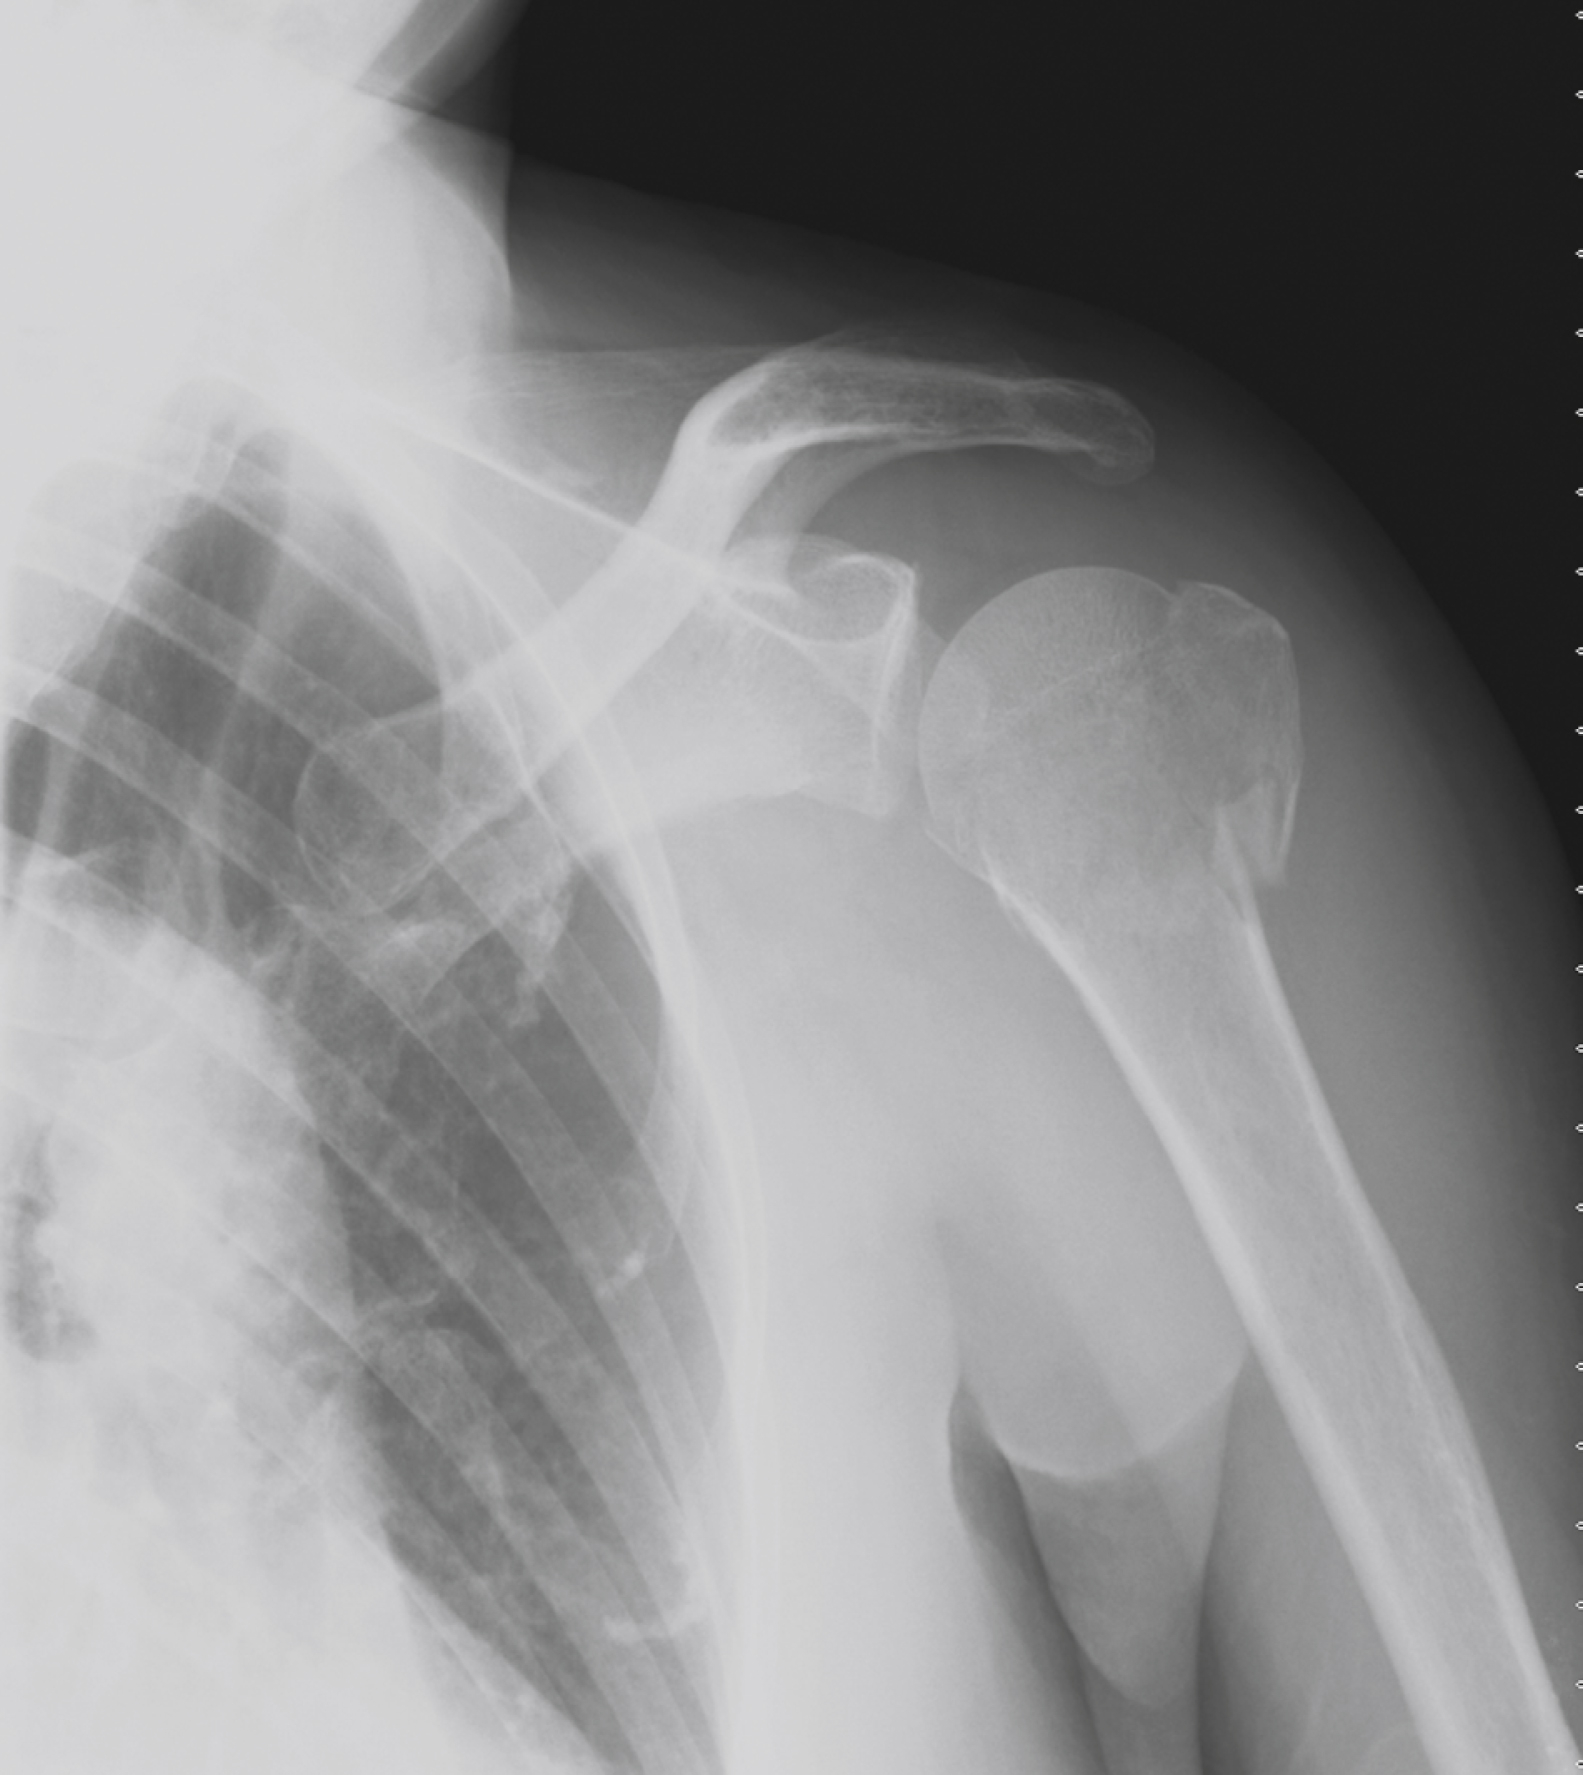

The clavicle accounts for 3% to 5% of all fractures with a 2:1 male to female ratio. It is also the most commonly fractured bone in children. Clavicular fractures are classified anatomically and mechanistically into three groups. Fractures of the medial third are uncommon (5%) and occur as a result of a direct blow to the anterior chest. Fractures of the middle third are the most frequent ( Figs. 45.6 and 45.9 ), accounting for 80% of all injuries. The usual mechanism of injury involves a direct force applied to the lateral aspect of the shoulder as a result of a fall, sporting injury, or motor vehicle collision (MVC). Fractures of the lateral third (15%) result from a direct blow to the top of the shoulder and are classified further into subtypes. Type I fractures are stable and minimally displaced because the coracoclavicular ligament remains intact. Type II fractures are associated with a torn coracoclavicular ligament and have a tendency to displace because the proximal fragment lacks any stabilizing forces ( Fig. 45.7 ). Type III injuries involve the articular surface.

Displaced Midclavicular Fracture.

Type II lateral clavicular fracture and torn coracoclavicular ligament.

Courtesy Erik Foss, MD.